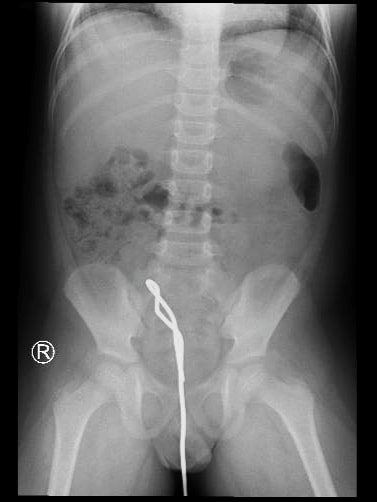

Bé trai 6 tuổi (Cần Giuộc, Long An) tiền căn thích nhét đồ vào hậu môn. Cách nhập viện 2 giờ, em vào nhà vệ sinh nhét thanh sắt thông cống vào hậu môn nhưng không rút ra được.

BS Nguyễn Thị Cẩm Xuyên và ekip bác sĩ của Bệnh viện Nhi đồng Thành phố đã khẩn trương nội soi ổ bụng thám sát thấy đoạn ruột sigma bị bầm máu, chưa thấy thủng ruột. Thăm hậu môn thấy cái cạnh sắt ghim chặt vào thành sau trực tràng.

Cách nhập viện 2 giờ, em vào nhà vệ sinh nhét thanh sắt thông cống vào hậu môn nhưng không rút ra được.

Kết hợp ngả bụng và hậu môn lấy thanh sắt ra ngoài theo ngả hậu môn. Sau mổ, bệnh nhi đang được ổn định sức khoẻ, thăm khám tâm lý, đang nhịn ăn theo dõi tiếp diễn tiến chảy máu hoặc thủng xước đường ruột.

Cạnh sắt của cây thông cống ghim chặt vào thành sau trực tràng.